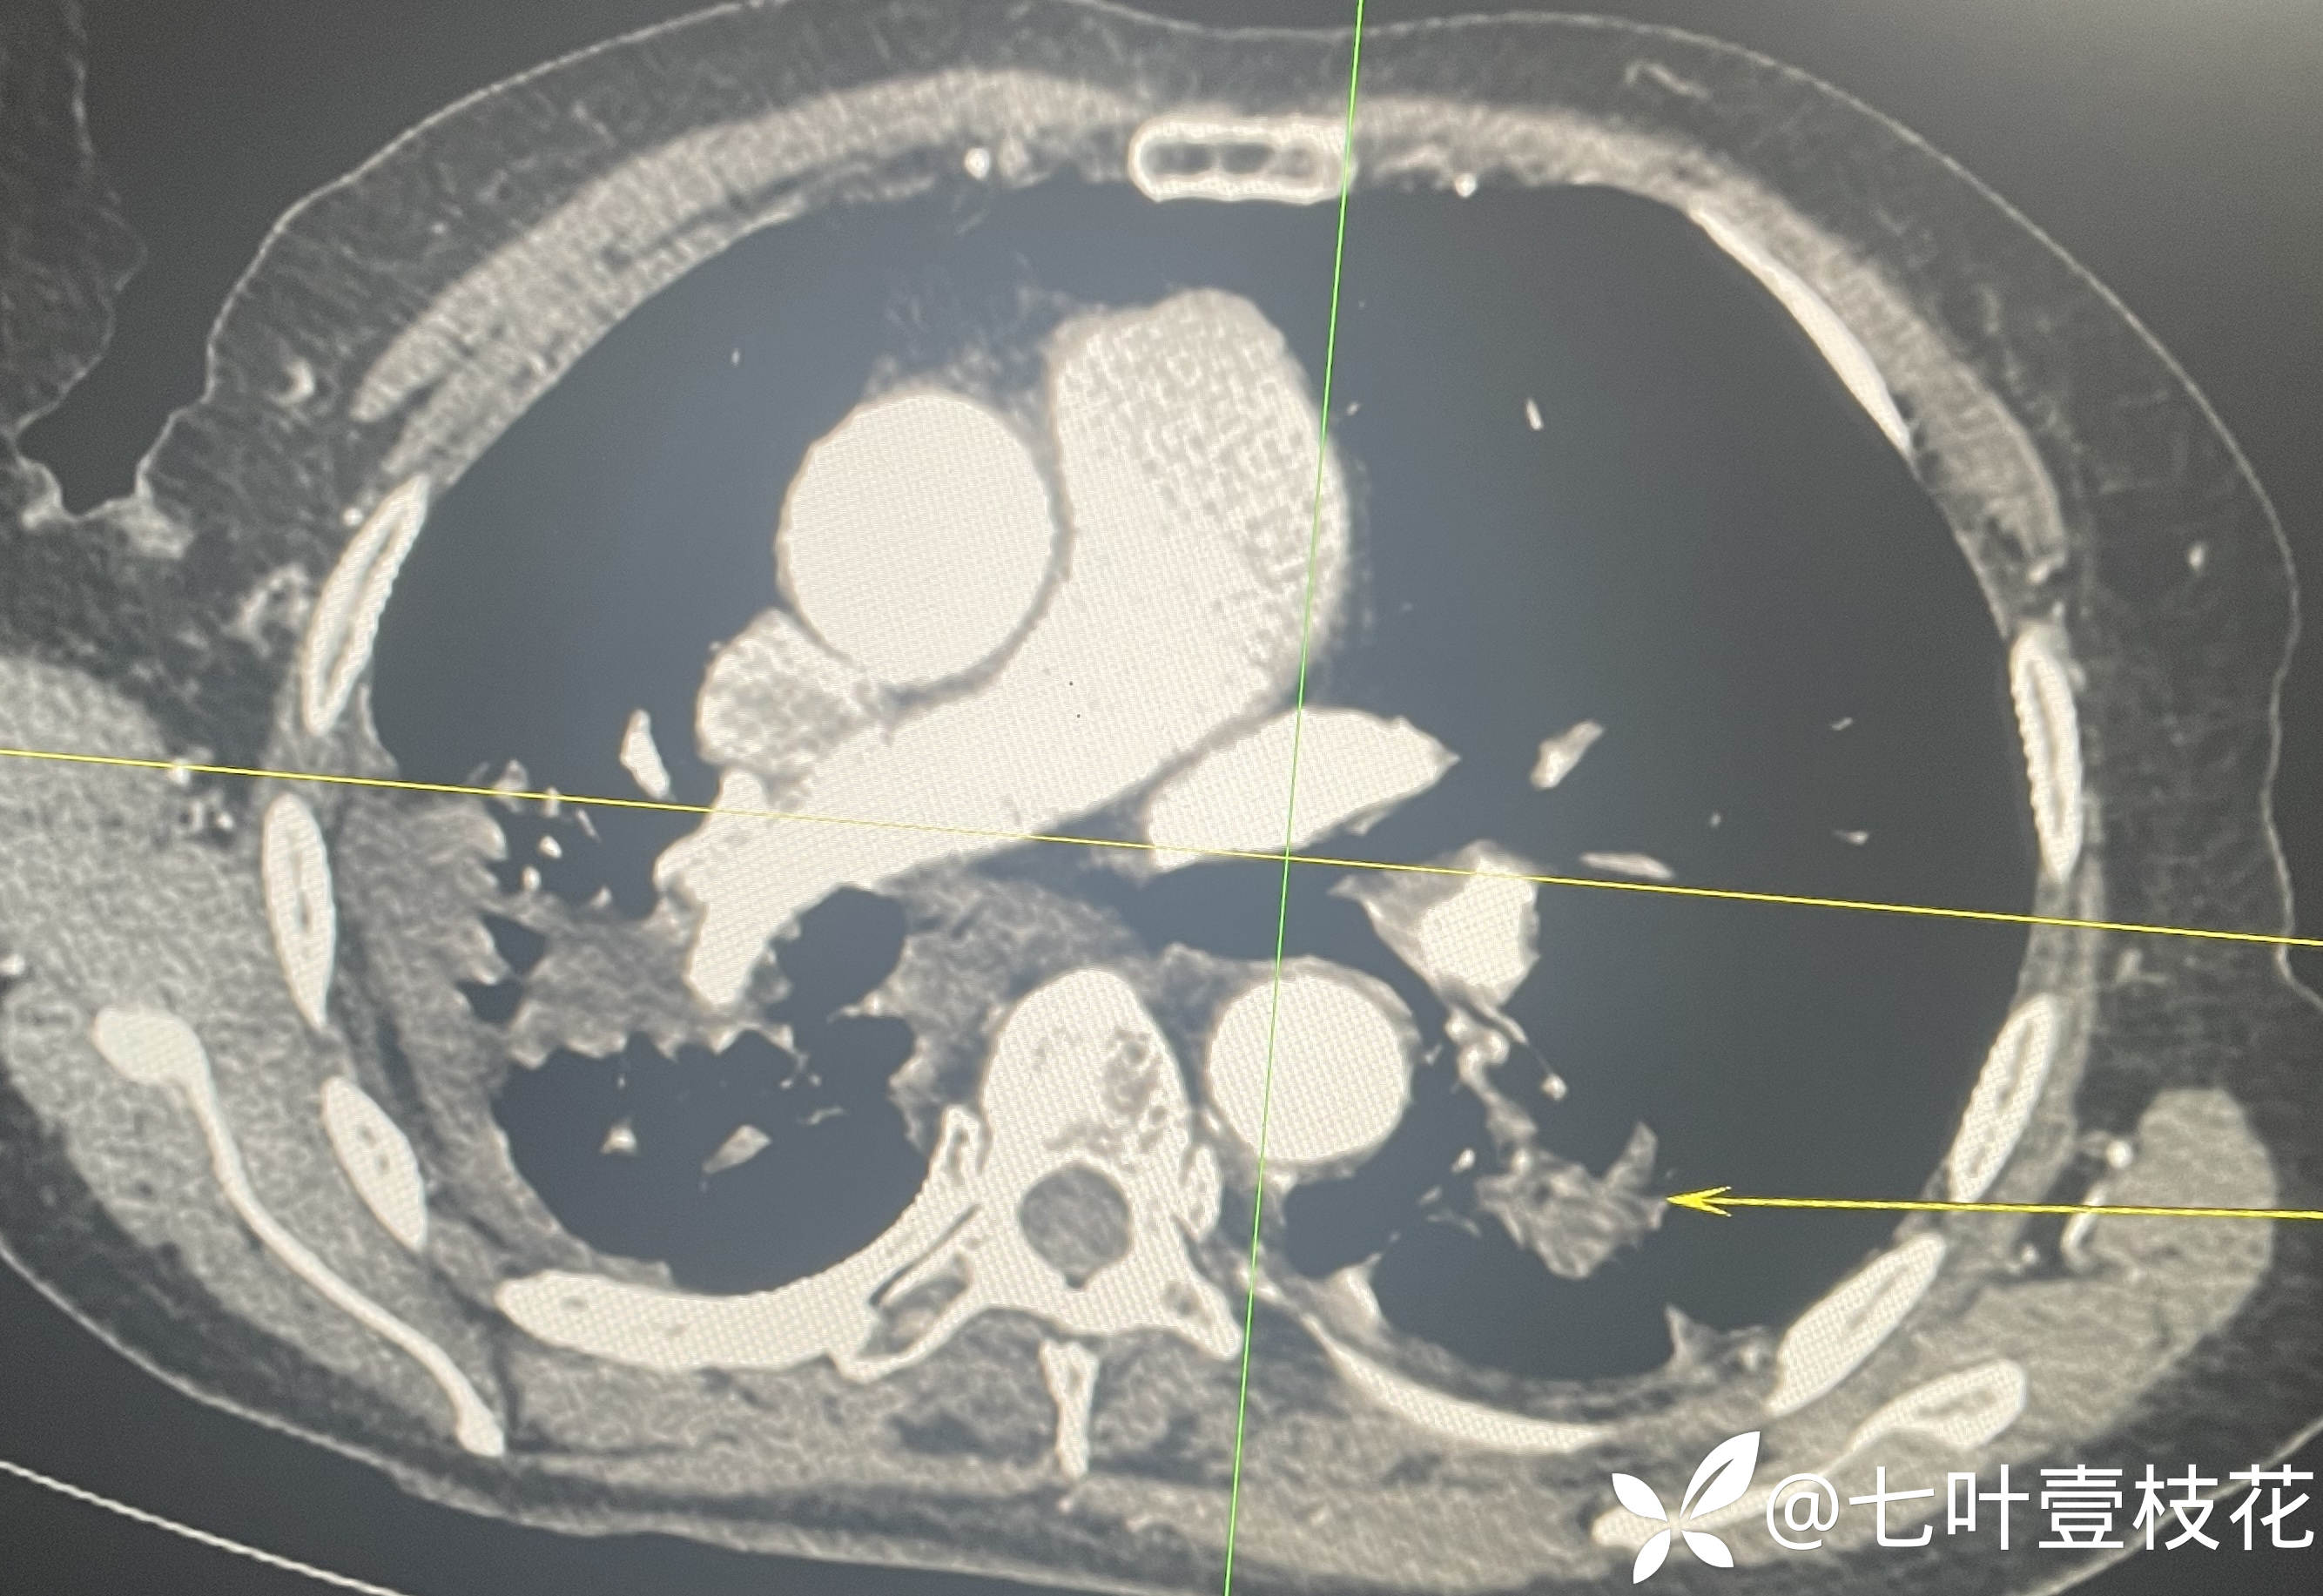

8月5日,入院第一天全腹CT

下面是腹主动脉CTA动态视频(动脉期和静脉期)及文字报告:

8月7日,入院第三天腹主动脉CTA

这位患者是8月5日凌晨入院的,第二天完善了肠镜,经治疗后到8月6日未再便血,腹痛也有所缓解,8月7日出现解黄色稀水样便3次,每次约100-200ml,其内可见少许类似肠道组织样絮状物,腹痛加剧,后来完善腹主动脉CTA后转上级医院进一步治疗了。病检目前未回,上级医院检查结果后续随访补充。